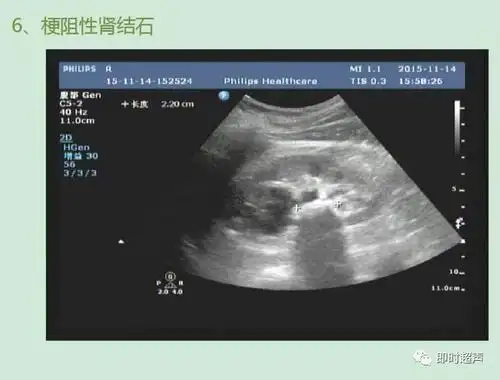

肾结石超声诊断及鉴别